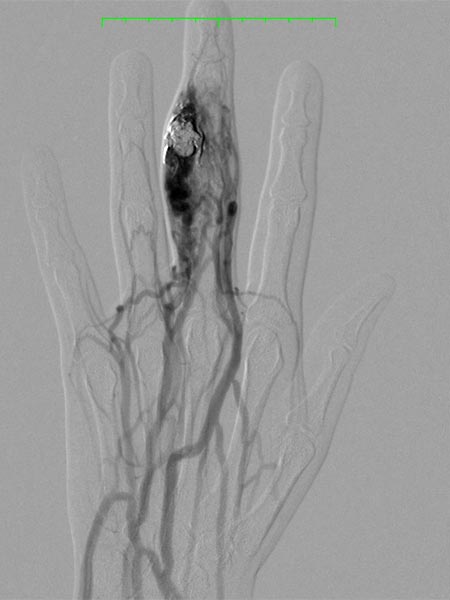

Angiographic control of the right hand with catheter injection from transarterially via the ulnar artery. Complete devascularization of the AVM nidus. No fast-flow shunts can be angiographically detected. The treated AVM with occluded nidus is thus resectable.

Fluoroscopic view of the cast after successful nidus embolization of the AVM. To improve the overview for surgical planning, this image is also shown without subtraction with visible bone.